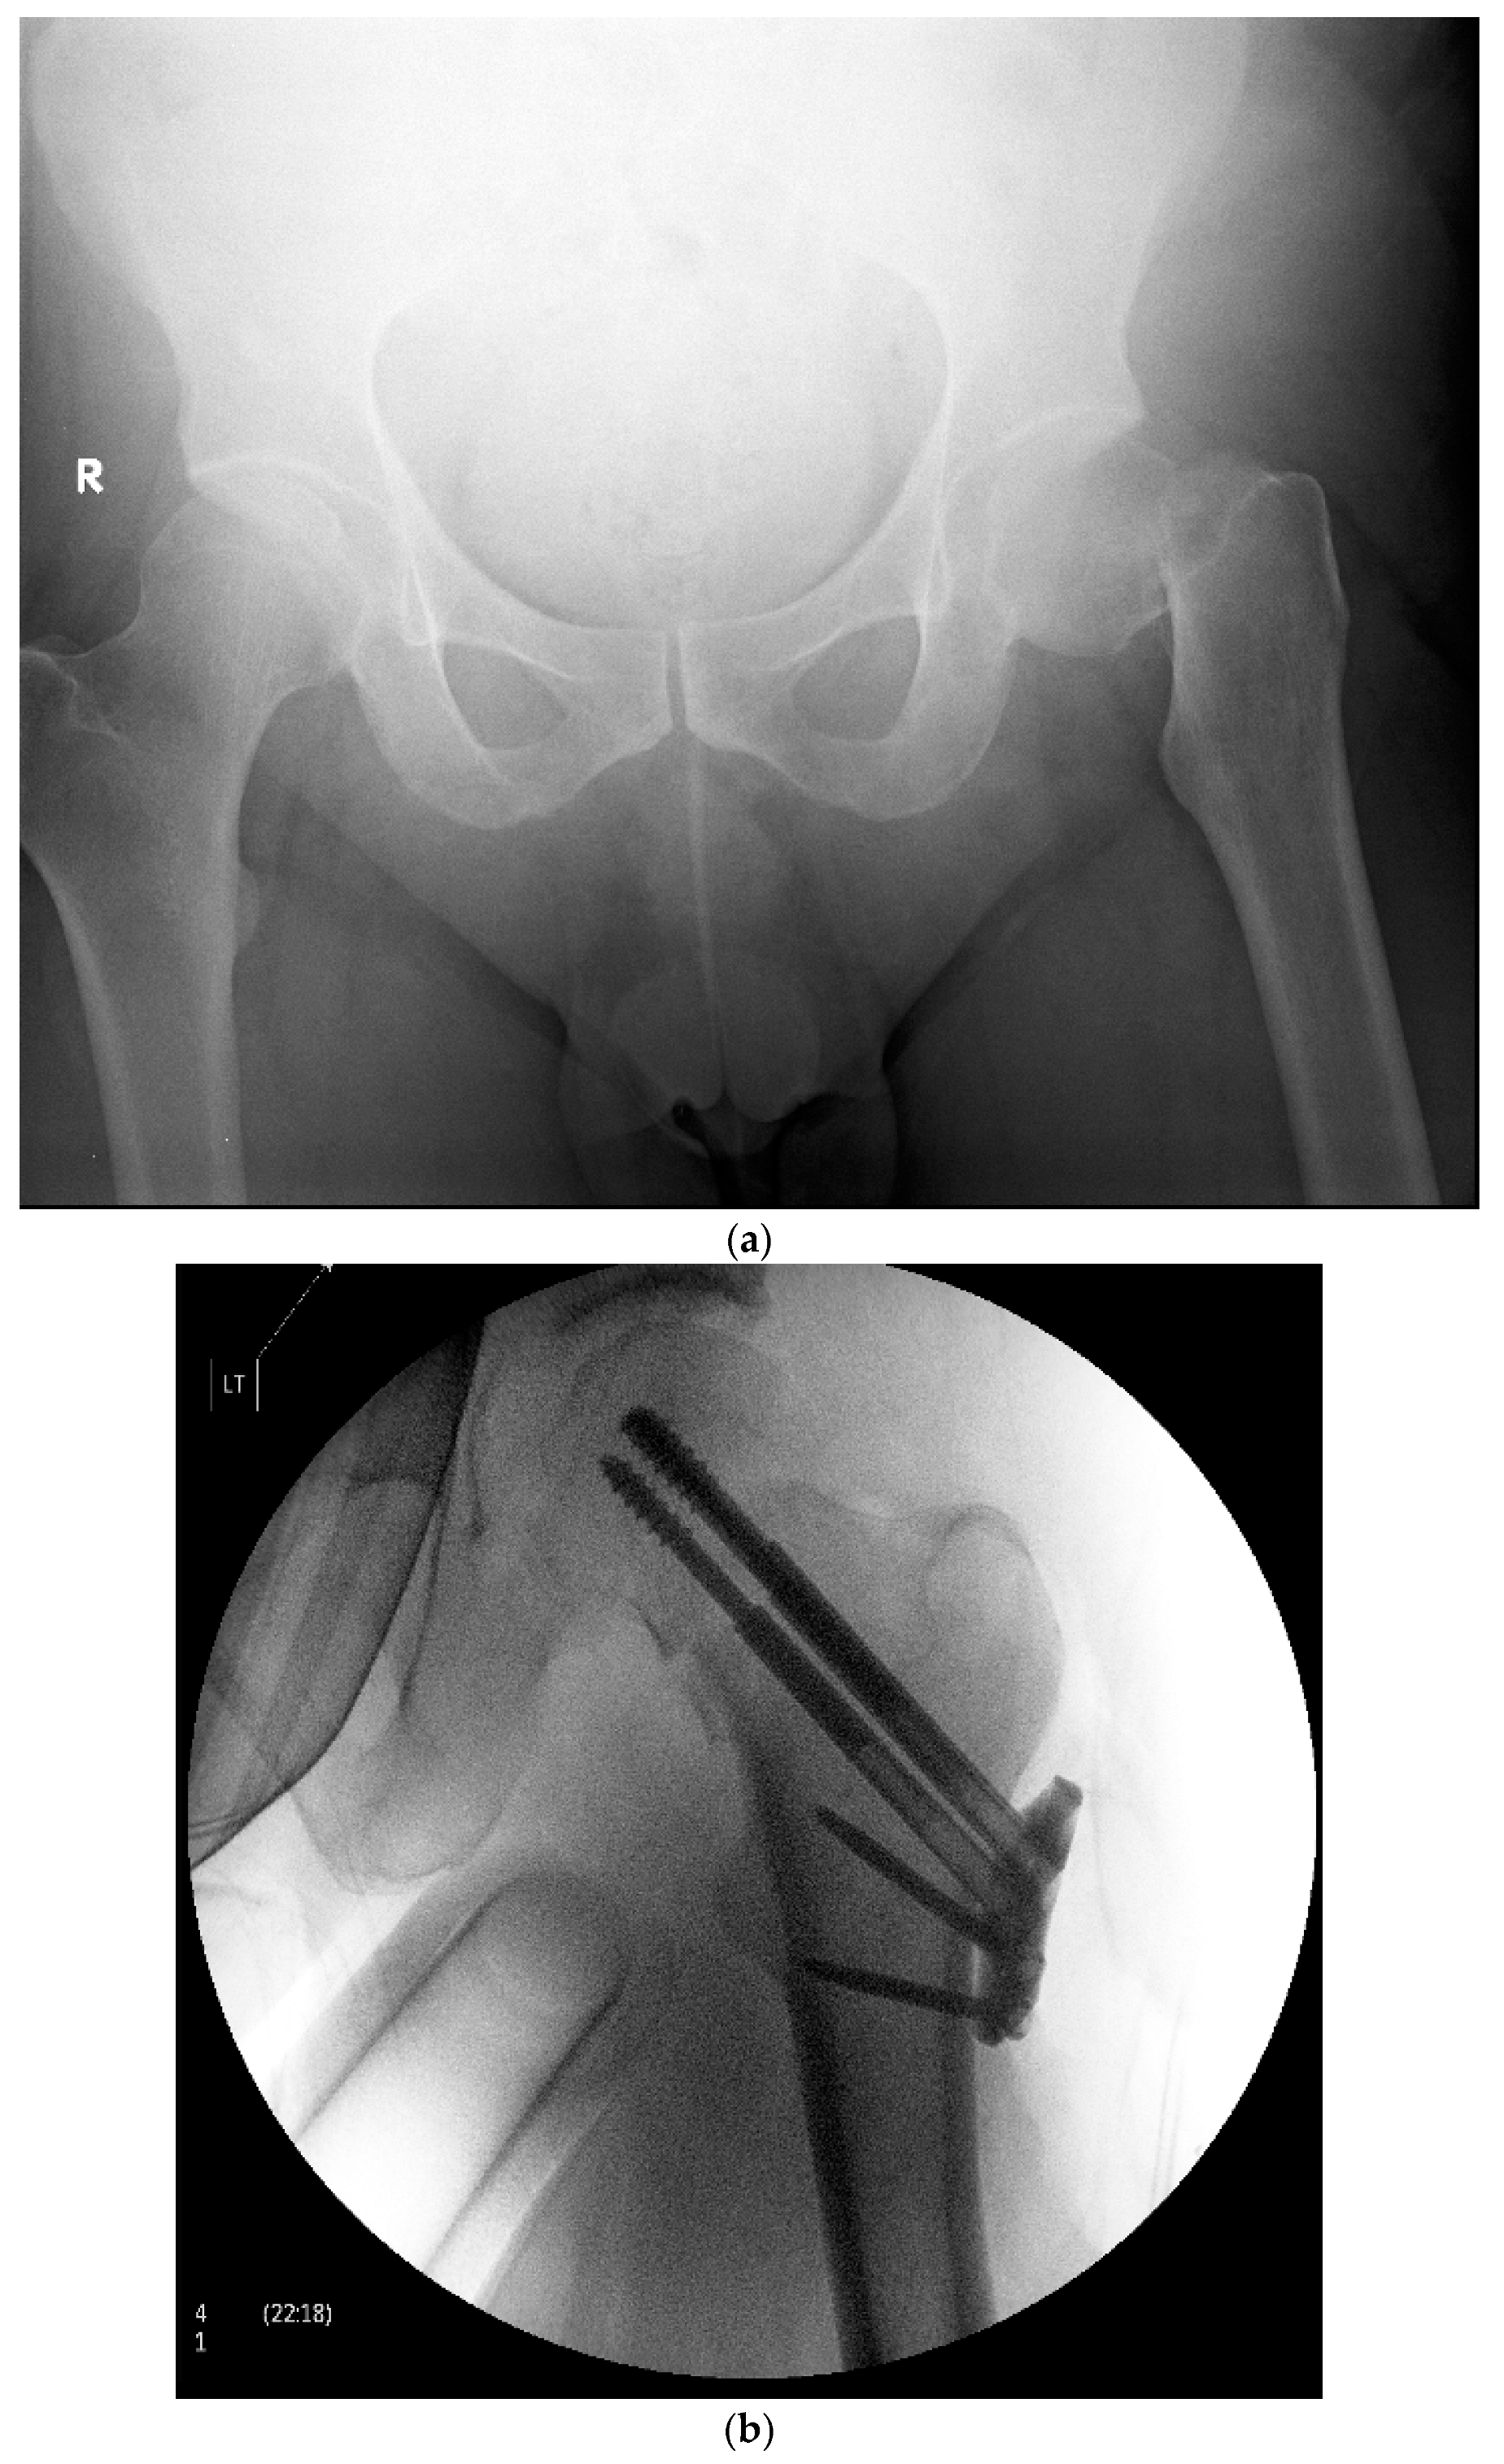

Figure 2.

(a)—Pre-operative X-ray demonstrating a left sided displaced femoral neck fracture in a 48-year-old male. R—Patient’s right side. (b)—Postoperative X-ray demonstrating operative fixation of the same fracture with the Targon FN system. LT—Patient’s left side.